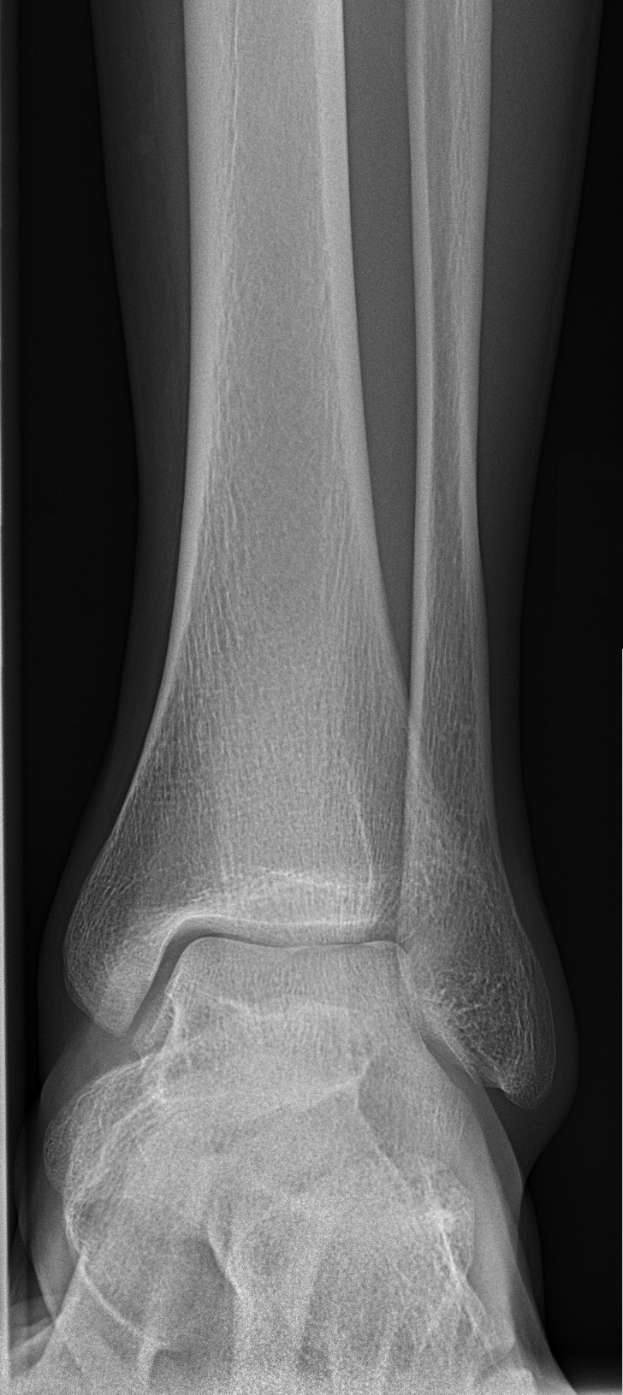

Der 20-jährige Abwehrspieler zog sich am Sonntag, dem 14. März 2026, in einem Spiel der Regionalliga West einen komplizierten Knöchelbruch zu. Die Verletzung bedeutet einen herben Rückschlag für seine Entwicklung sowie für die U23-Mannschaft des FC Schalke 04.

Laut Berichten handelt es sich um einen schweren Knöchelbruch, der eine langwierige Rehabilitation erfordert. Zwar hat Schalke keine Änderungen in der Transferplanung angekündigt, doch die Verletzung bremst Khadrs Aufwärtstrend in einer entscheidenden Phase seiner Karriere aus.